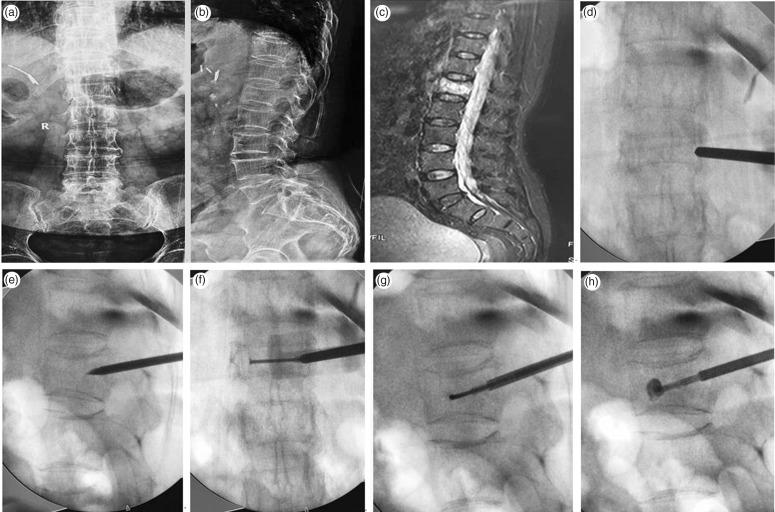

Patients with thoracolumbar OVCFs were recruited and randomly divided into three treatment groups: PCVP, unilateral percutaneous vertebroplasty (PVP) or bilateral PVP. Bone cement dispersion in the fractured vertebrae was observed. Surgery duration, X-ray frequency, bone cement injection volume, bone cement leakage rate and visual analogue scale (VAS) scores were recorded.

Among 78 patients included, surgery duration and X-ray frequency were significantly lower in the PCVP and unilateral PVP groups versus bilateral PVP group. Bone cement injection volume was significantly higher in the bilateral PVP group (6.3 ± 1.4 ml) versus unilateral PVP (3.5 ± 1.1 ml) and PCVP groups (4.6 ± 1.2 ml). VAS scores at 24 h and 3 months post-surgery were significantly decreased versus baseline in all groups. The bone cement leakage rate was lowest in the PCVP group (8.8% [3/34 patients]).

PCVP is associated with reduced trauma, less complicated surgery with shorter duration, fewer X-rays, lower complication rate, and quicker postoperative recovery versus unilateral and bilateral PVP.